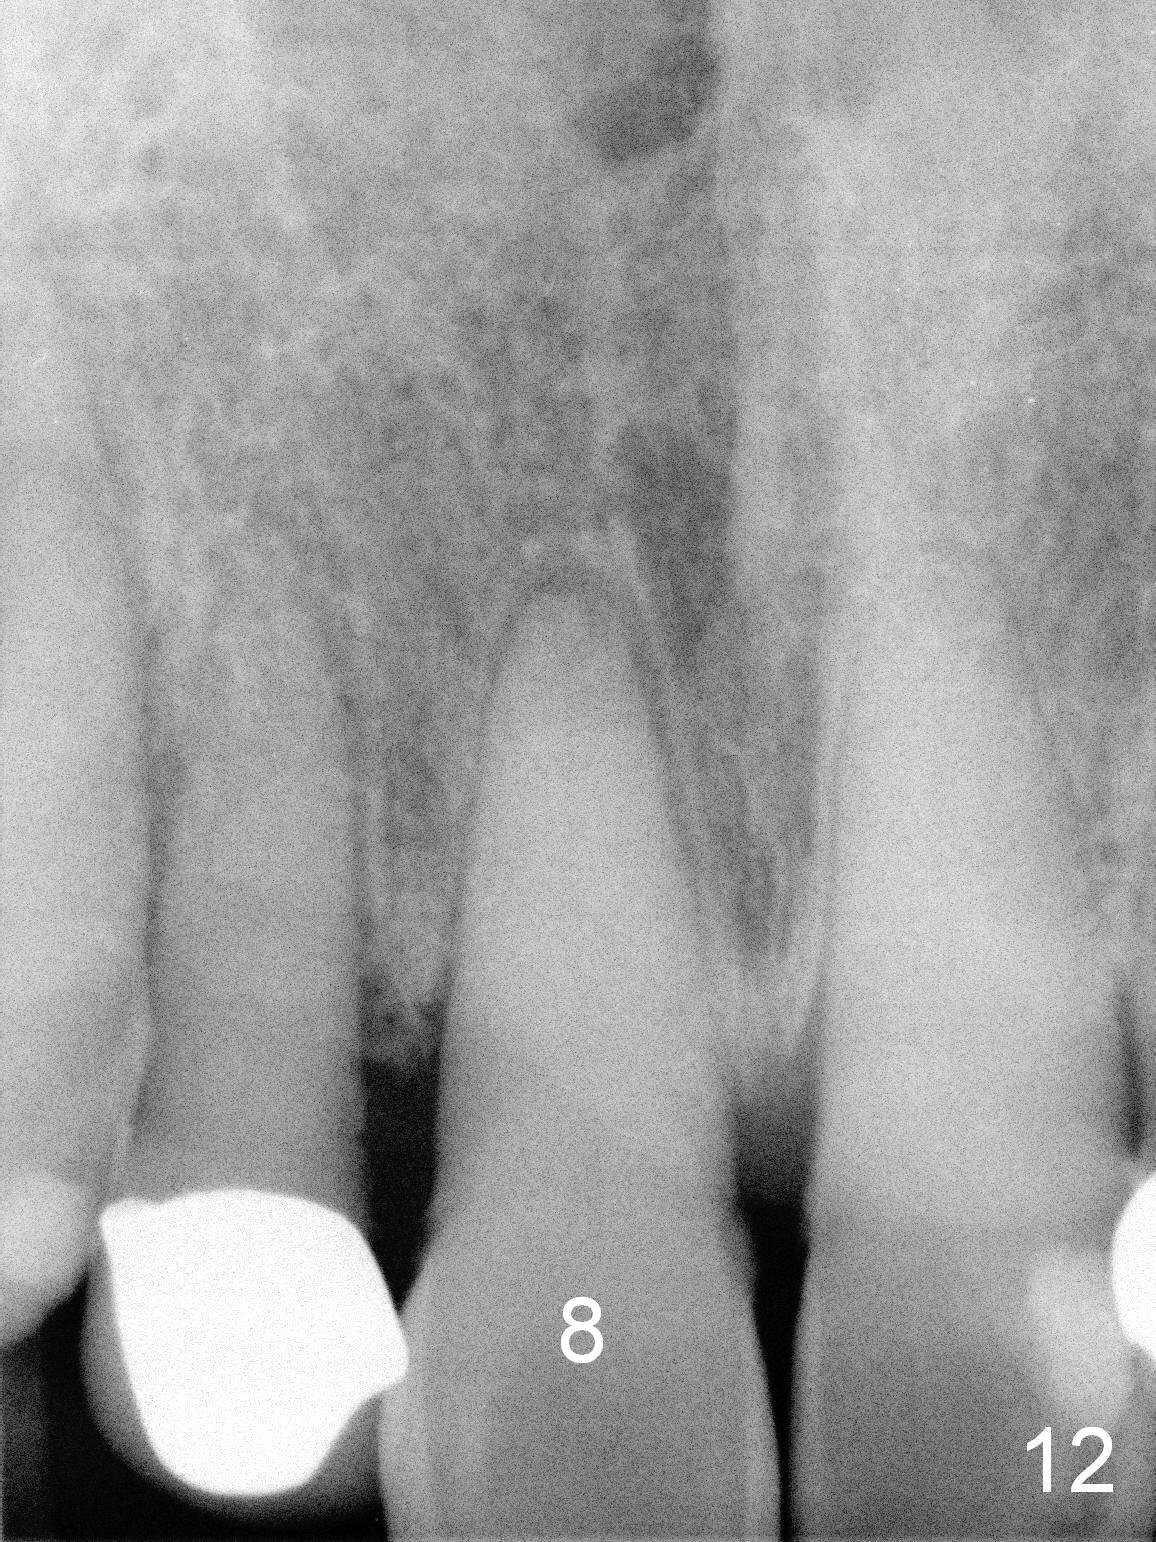

Although the patient feels better after taking Amoxicillin, the infection remains at #6-8 five weeks postop (Fig.12,13). The tooth #8 appears to be extruded with >10 mm buccal pocket. Water pik is recommended. It seems that the teeth #6-8 should be extracted and replaced with implants. Scaling & root planing should be tried first (Fig.11,12).

Two months and a half postop (#3,5 implantation), the patient agrees to have #6-8 to be extracted because of persistent infection. She reports dislodgement of the provisional at #3-5 using water pik. The provisional is found to be mobile. PA shows decrease in bone density around the implant at #5, probably due to proximity to the infection (Fig.14 *).